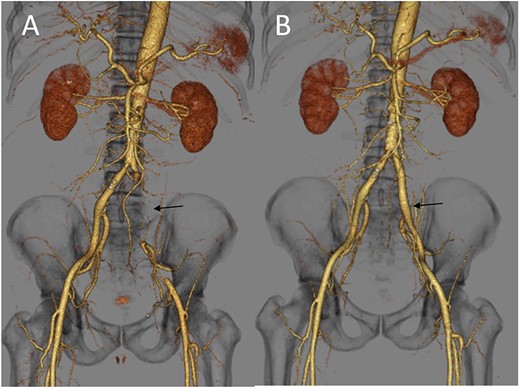

(A) Three-dimensional enhanced CT image obtained immediately after developing acute limb ischemia. The left iliac artery was occluded as indicated by an arrow. (B) Three-dimensional enhanced CT image obtained on post-operative day 11. A patent left iliac artery was observed, as indicated by an arrow.

The patient underwent urgent thrombectomy to salvage the left lower limb. Using a Fogarty catheter, fresh thrombus in the left iliac artery and superficial femoral artery was removed. The patient’s hypoxia condition continued until post-operative day 4. From post-operative day 6, coumadin was initiated to treat the remaining thrombus in the aorta (Fig. 1C). After confirming a negative test result for COVID-19, the patient was discharged on post-operative day 20. A month after the surgery, repeat enhanced CT showed a decrease in the quantity of intra-aortic thrombus (Fig. 1D) and the patent left iliac artery (Fig. 2B).